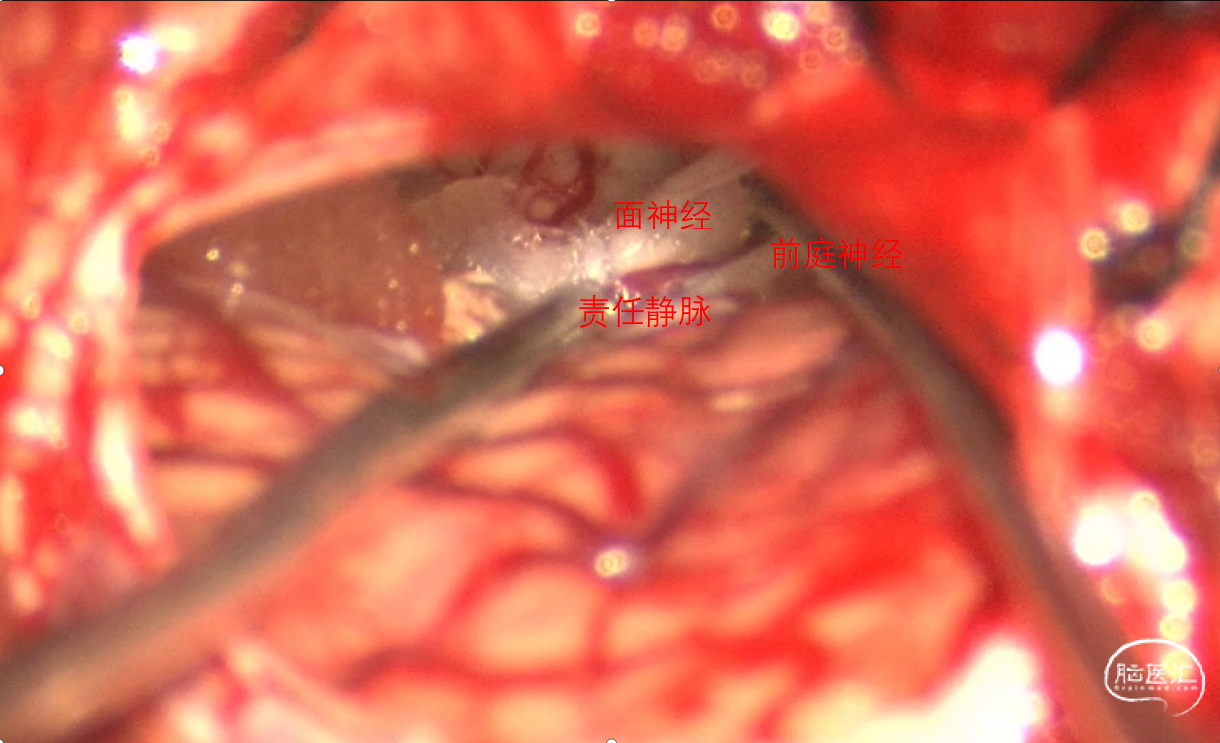

手术过程:常规侧卧位,乙状窦后发迹内直切口约6cm,星点前下方钻孔后铣刀游离骨瓣,磨钻扩大骨窗达乙状窦后缘,剪开硬脑膜后脑组织饱满释放脑脊液后仍不能显露CPA结构,遂将颅骨进一步磨除显露部分乙状窦,形成扩大乙状窦后入路,同时调整头位和显微镜进一步增加对CPA区的显露,在牵开小脑半球释放桥前池脑脊液后颅压下降脑组织塌陷。从后组颅神经处锐性剪开蛛网膜,暴露REZ区未见明显动脉压迫,只有小脑中脚静脉由桥脑于面听神经之间穿行后进入桥静脉汇入颈静脉孔。向后组颅神经腹侧、桥延沟及内听道处探查无动脉压迫,确认单纯静脉压迫。小块的垫棉小心垫于面神经和静脉之间后电生理提示除眼轮匝肌外其余LSR消失,电生理实时监护下反复调整垫棉位置最终LSR消失。水密缝合硬脑膜,骨瓣复位固定,各层严密缝合。术后患者清醒后面部抽搐未发作,听力正常,无面瘫。

于面神经与静脉间置入垫棉在电生理护航下反复调整垫棉位置最终LSR消失。

通过查阅Rhoton anatomy我们认为此例病人责任血管为小脑中脚静脉。

静脉血管压迫导致的面肌痉挛在临床工作中少见,文献中多为个案报道,缺乏大宗病例报道,其发病率在0-5.5%,也有静脉联合蛛网膜束带导致的面肌痉挛的报道,静脉压迫的MVD其手术操作较动脉血管难度增加,手术操作要求高,但原则是一样的,达到减压隔绝的目的即可,因静脉血管易出血所以动作要轻柔,避免静脉撕裂,在电生理监测下实时观察LSR的变化是手术核心。在3D-TOF-MRA检查怀疑静脉压迫且LSR阳性的患者可以进行MVD手术治疗。